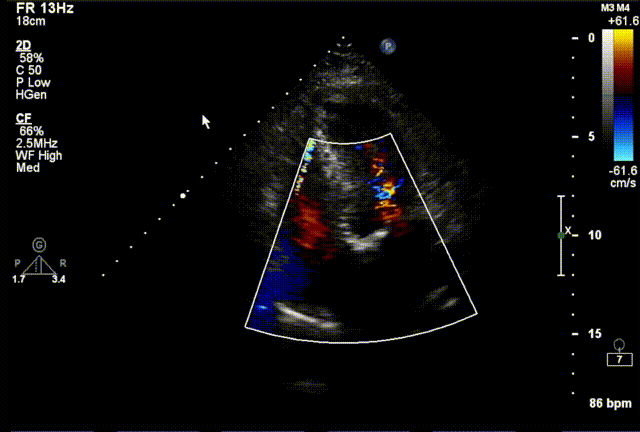

术后超声